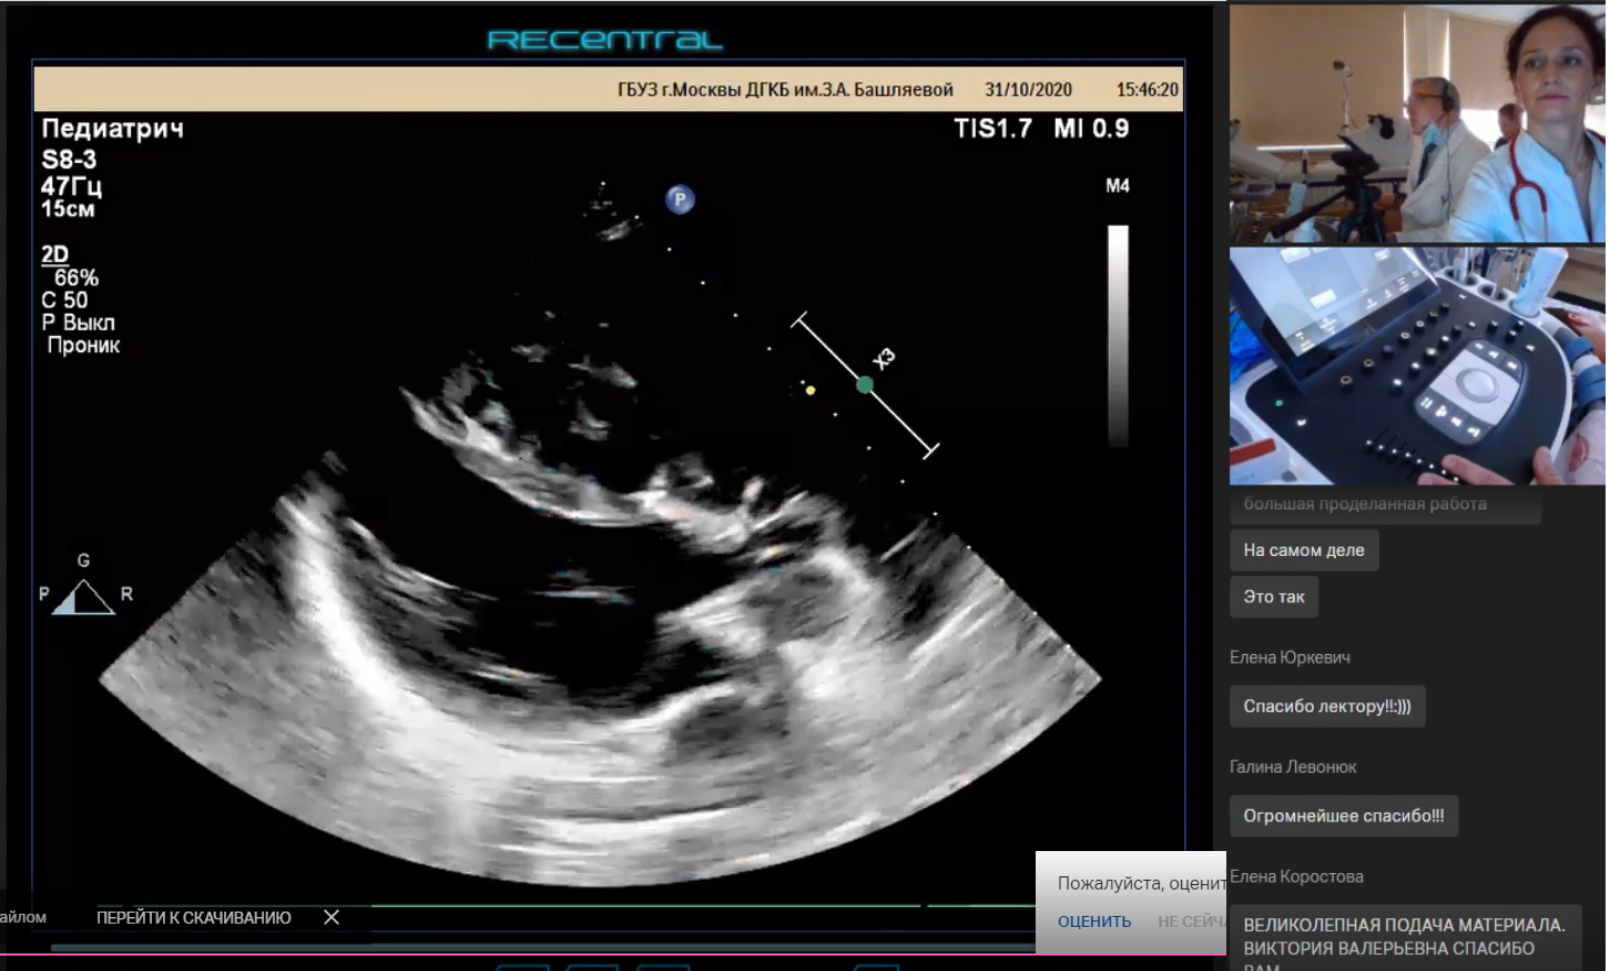

30–31 октября 2020 года по инициативе главного внештатного специалиста детского кардиолога ДЗМ Москвы, д. м. н. Труниной Инны Игоревны на базе ДГКБ им. З. А. Башляевой ДЗМ успешно прошел двухдневный курс «Клиническая эхокардиография в диагностике кардиологических заболеваний детского возраста». Сотрудники ОМО по педиатрии НИИОЗММ ДЗМ приняли активное участие в организации и проведении образовательного мероприятия.

Курс создан для детских кардиологов, врачей ультразвуковой диагностики и других специалистов, которые встречаются в своей работе с необходимостью проведения эхокардиографии детям. Его целью являлись обучение врачей принципам ранней диагностики заболеваний сердца у детей, унификация протокола эхокардиографического исследования и совершенствование вопросов преемственности между специалистами амбулаторного и стационарного звена.

В программе курса освещалась диагностика сложных врожденных пороков сердца, легочной гипертензии, патологии коронарных артерий и новообразований сердца, оценка деформации миокарда и функции протезированных клапанов сердца.

В течение двух дней ведущие специалисты по детской ультразвуковой диагностике представили актуальный теоретический материал по ключевым темам, вызывающим диагностические сложности у врачей практического звена, и провели мастер-классы (практические занятия) с разбором сложных пациентов и возможными ошибками диагностики.